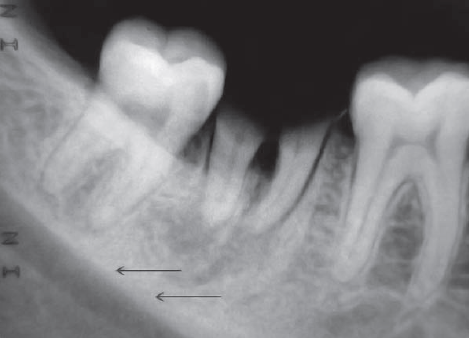

53. What is showing by arrow?

Inferior Alveolar Canal appears as a dark linear shadow with thin radiopaque superior and inferior borders cast by the lamella of bone that bounds the canal